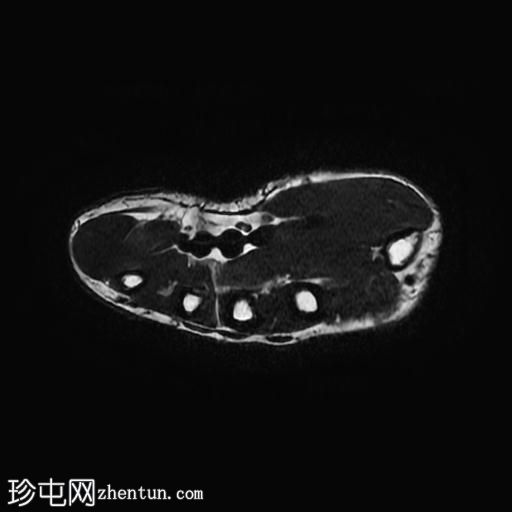

轴位PD脂肪抑制像

7.jpg

拇指长伸肌腱远端近乎完全撕裂,撕裂部位位于指间关节和远节指骨基底部,伴有拇指屈曲畸形。

近端撕裂端位于近节指骨颈部附近,撕裂端之间约有9毫米的间隙。

拇指近节指骨基底部以及第一掌骨头颈部可见骨髓水肿。

此外,第一掌指关节水平的尺侧副韧带显示异常的实质内液体信号增高和增厚,与尺侧副韧带扭伤有关。